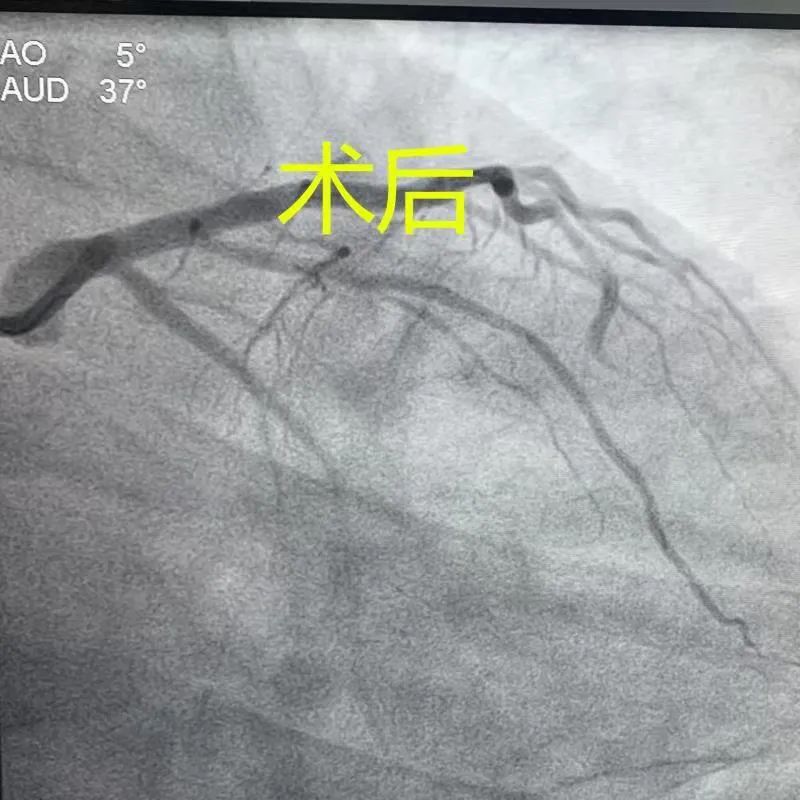

時(shí)間就是心肌,時(shí)間就是生命!患者到院后,急診科主任解治峰快速閱讀心電圖后,帶著搶救藥一路小跑直接將患者推入導(dǎo)管室。心內(nèi)一科主任金禮彪、副主任閔碧秋、醫(yī)生姜松柏、導(dǎo)管室工作人員已做好手術(shù)準(zhǔn)備,閱讀相關(guān)輔助檢查后確定有手術(shù)適應(yīng)癥無(wú)禁忌癥,立即開(kāi)始進(jìn)行冠脈血管造影檢查,結(jié)果顯示患者心臟前降支近段血管完全堵塞,隨時(shí)都有生命危險(xiǎn),必須立即開(kāi)通血管!